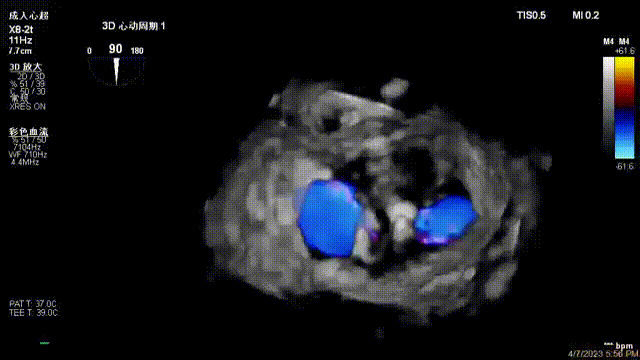

接受治療的是一例器質性重度二尖瓣反流(DMR)患者,主訴“反復活動后胸悶,氣促3年余”。術前超聲顯示,雙房增大,二尖瓣脫垂伴重度反流,輕度三尖瓣反流,輕度肺高壓,升主動脈增寬。手術經股靜脈-房間隔入路,采用全身麻醉插管,在TEE和DSA引導下完成房間隔穿刺。置入JensClip瓣膜夾系統后,在左房調整瓣膜夾的位置和軸向,后進入左室,在TEE引導下捕捉二尖瓣前后瓣葉,并關閉瓣膜夾。經TEE反復確認手術效果后最終鎖定并釋放瓣膜夾。術后即刻超聲顯示瓣膜夾位置穩定,功能良好,術前二尖瓣反流4+,術后0反流,肺靜脈逆流和左房壓都顯著好轉,手術圓滿成功(以上數據都來源于醫院的臨床記錄)。術后患者狀態良好,目前已安排出院。

出院前隨訪超聲